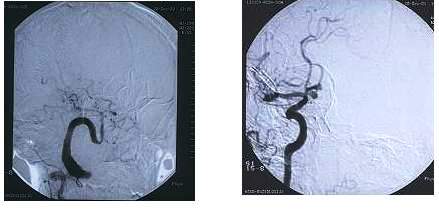

Invazivne dijagnostičke metode su pre svega angiografija, klasična kao

i digitalna subtrakciona, zatim LP - lumbalna punkcija. Ove invazivne

metode, posebno angiografija, primenjuju se tek nakon što su primenjene

neinvazivne, ukoliko dati slučaj zahteva to, u cilju definitivnog dijagnostičkog

razrešnjenja slučaja.

Angiografija krvnih suda glave i vrata nam pokaže stanje krvnih žila,

kao i eventualne promene na njima u smislu aneurizme ili arteriovenske

malformacije.

Angiografija krvnih suda glave i vrata